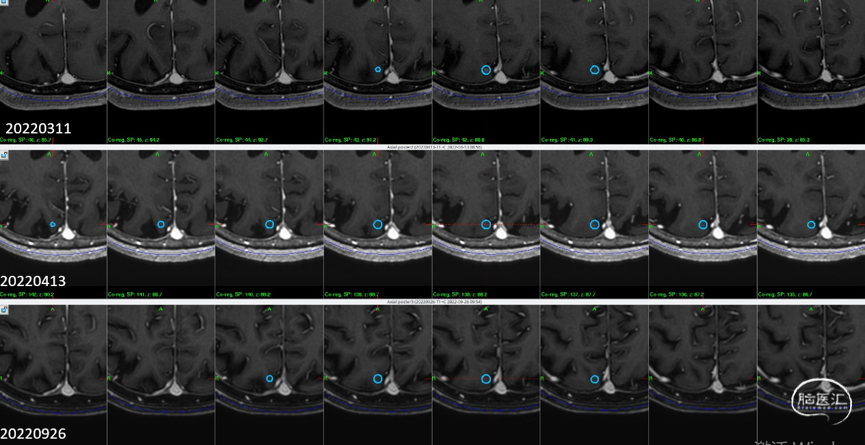

2)右侧侧脑室壁病灶体积缩小显著:

再次伽玛刀治疗

6个月随访

影像随访:

6个月随访时,薄扫增强磁共振(1mm/层)提示肿瘤明显缩小,无放射相关不良反应,没有新发病灶;患者目前仍在规律的随访当中,期待我们的长期随访结果。